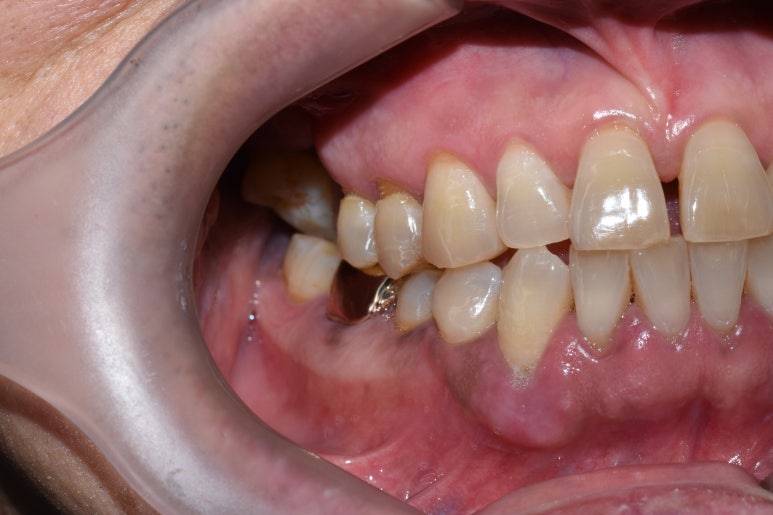

↑치료 전 사진입니다. 큰 어금니 쪽에 치아들이 성하지 않아

씹기가 힘든 상태입니다.